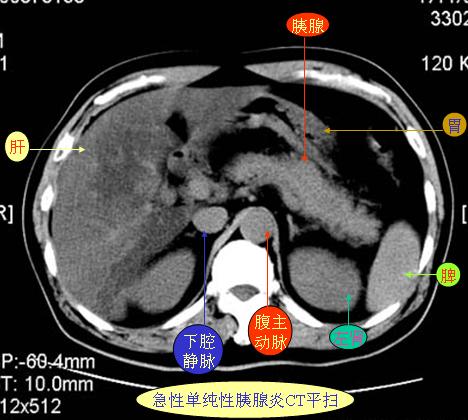

腹部ct解剖与基本病变